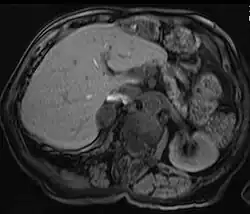

Liver

Hepatic adenomas are a rare benign tumour of the liver, which may present with hepatomegaly or other symptoms.